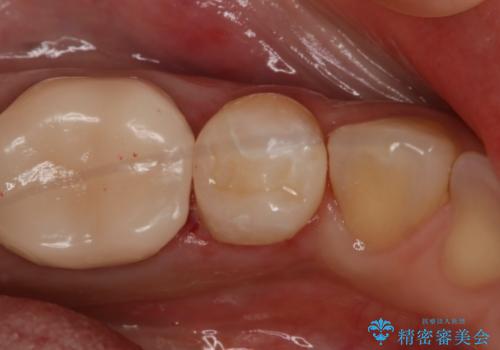

形態、切削量などを考慮し、セラミックインレーにて治療を行いました。

メタルインレー、う蝕除去後にCRにて裏層した上で、形成・印象を行いました。